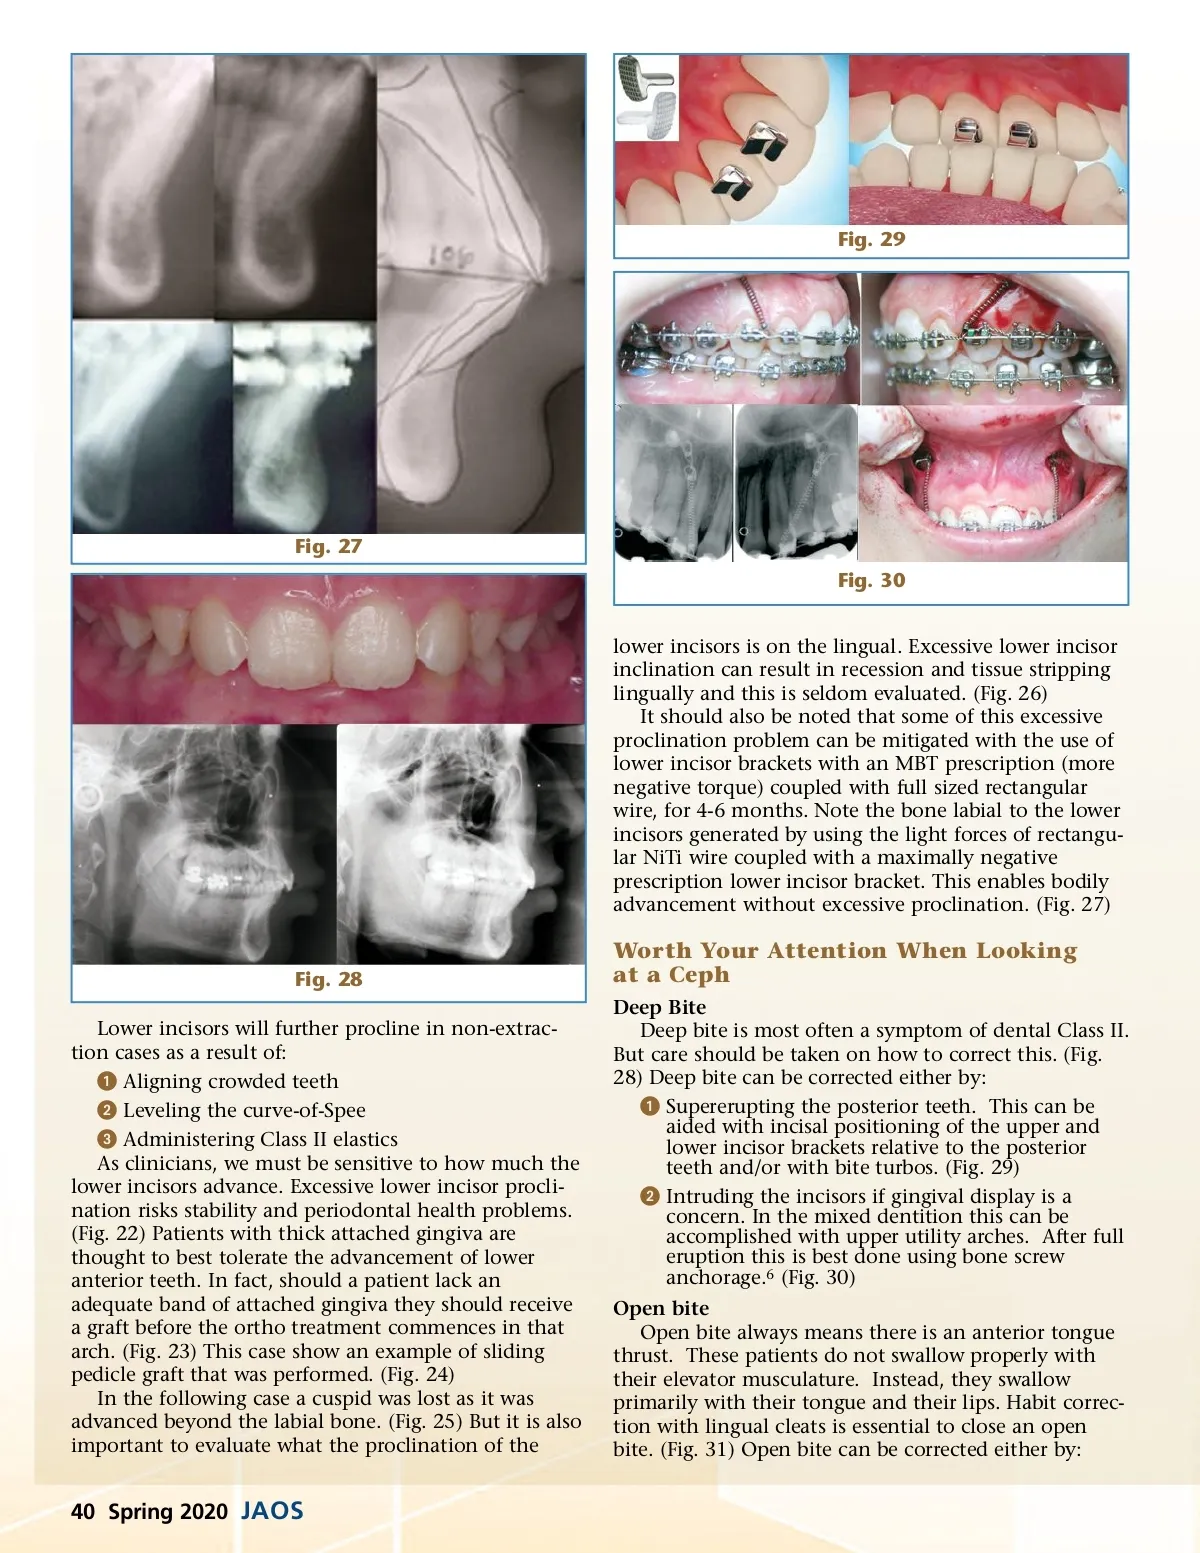

Fig. 29 Fig. 27 Fig. 30 lower incisors is on the lingual. Excessive lower incisor inclination can result in recession and tissue stripping lingually and this is seldom evaluated. (Fig. 26) It should also be noted that some of this excessive proclination problem can be mitigated with the use of lower incisor brackets with an MBT prescription (more negative torque) coupled with full sized rectangular wire, for 4-6 months. Note the bone labial to the lower incisors generated by using the light forces of rectangu-lar NiTi wire coupled with a maximally negative prescription lower incisor bracket. This enables bodily advancement without excessive proclination. (Fig. 27) Fig. 28 Lower incisors will further procline in non-extrac-tion cases as a result of: ᕡ Aligning crowded teeth ᕢ Leveling the curve-of-Spee ᕣ Administering Class II elastics As clinicians, we must be sensitive to how much the lower incisors advance. Excessive lower incisor procli-nation risks stability and periodontal health problems. (Fig. 22) Patients with thick attached gingiva are thought to best tolerate the advancement of lower anterior teeth. In fact, should a patient lack an adequate band of attached gingiva they should receive a graft before the ortho treatment commences in that arch. (Fig. 23) This case show an example of sliding pedicle graft that was performed. (Fig. 24) In the following case a cuspid was lost as it was advanced beyond the labial bone. (Fig. 25) But it is also important to evaluate what the proclination of the Worth Your Attention When Looking at a Ceph Deep Bite Deep bite is most often a symptom of dental Class II. But care should be taken on how to correct this. (Fig. 28) Deep bite can be corrected either by: ᕡ Supererupting the posterior teeth. This can be aided with incisal positioning of the upper and lower incisor brackets relative to the posterior teeth and/or with bite turbos. (Fig. 29) ᕢ Intruding the incisors if gingival display is a concern. In the mixed dentition this can be accomplished with upper utility arches. After full eruption this is best done using bone screw anchorage. 6 (Fig. 30) Open bite Open bite always means there is an anterior tongue thrust. These patients do not swallow properly with their elevator musculature. Instead, they swallow primarily with their tongue and their lips. Habit correc-tion with lingual cleats is essential to close an open bite. (Fig. 31) Open bite can be corrected either by: 40 Spring 2020 JAOS